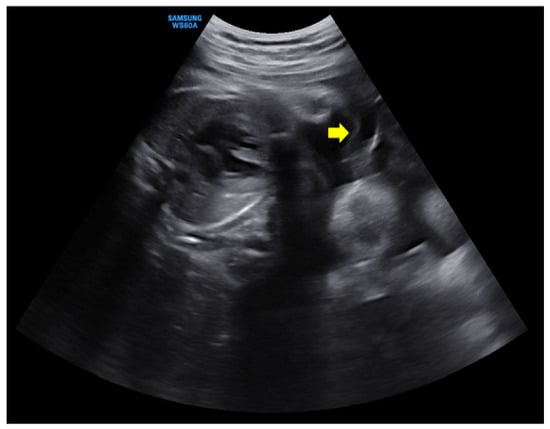

Figure 2. Ultrasonography was performed at admission. (A,B) showed the first fetus located on the left side of the mother. The fetal heart rate was 140–160 beats/min with good fetal motion, and amniotic fluid volume index (AFI) was more than 30 cm, showing polyhydramnios. (C,D) showed the second fetus located on the right side of the mother with breech presentation. The heart rate was 70–80 beats/min, showing a consistent bradycardia.

Initially, the patient’s vital signs were stable and as follows: blood pressure, 125/75 mmHg; pulse rate, 98 beats/min; respiratory rate, 20 breaths/min; body temperature, 36.6 °C; and oxygen saturation, 99%. Cervical examination revealed 10% cervical dilatation, 50% effacement, and −2 fetal station. Ultrasonography showed that the first fetus was located on the left side of the mother in a vertex presentation and that the fetal heart rate was 150–160 beats/min with good fetal motion, but the amniotic fluid volume index (AFI) was more than 30 cm, showing polyhydramnios. The second fetus was located on the right side of the mother and exhibited a heart rate of 70–80 beats/min and consistent bradycardia with a breech presentation, showing oligohydramnios (Figure 2). No evidence of placental abruption was noted. Continuous fetal monitoring was performed while preparing for an emergency cesarean section, and continuous fetal bradycardia of the second fetus was noted as 30–40 mmHg of uterine contractions at 5–6-min intervals.